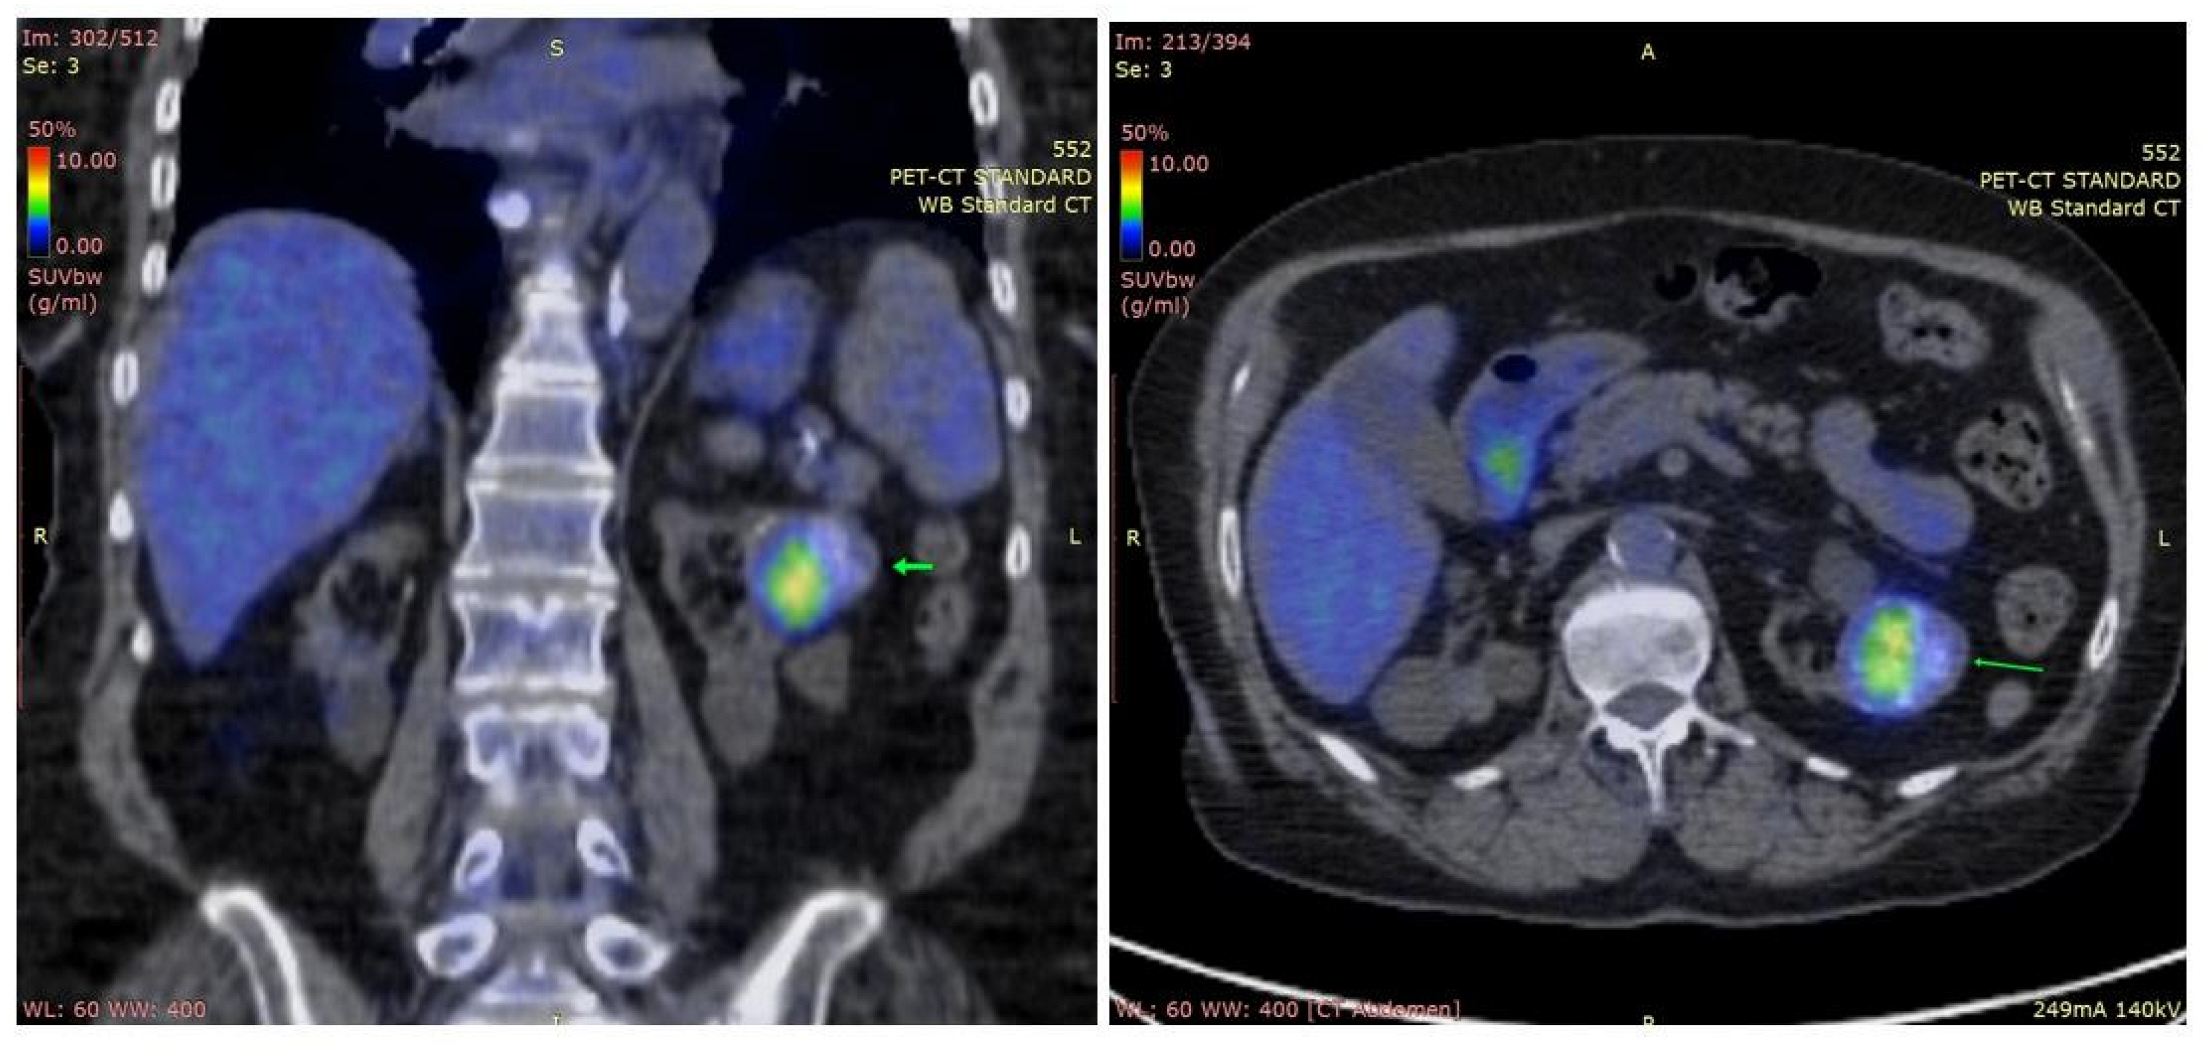

PTH levels showed an important early postsurgical drop but tended to increase at 6 and 9 months, despite normal levels of calcium (Table 1). Consequently, a positron emission tomography-computed tomography scan (PET-CT) was performed, showing a metabolically active, heterogeneous, renal mass with calcifications of 37/39/36 mm (Figure 3). Further investigations are needed to distinguish between primary renal lesion and PC metastasis.

Figure 3.

Positron emission tomography: abdominal coronal and axial sections; heterogeneous left renal mass with calcifications, metabolically active (maximum standardized uptake value = 6.3 g/mL; arrows).